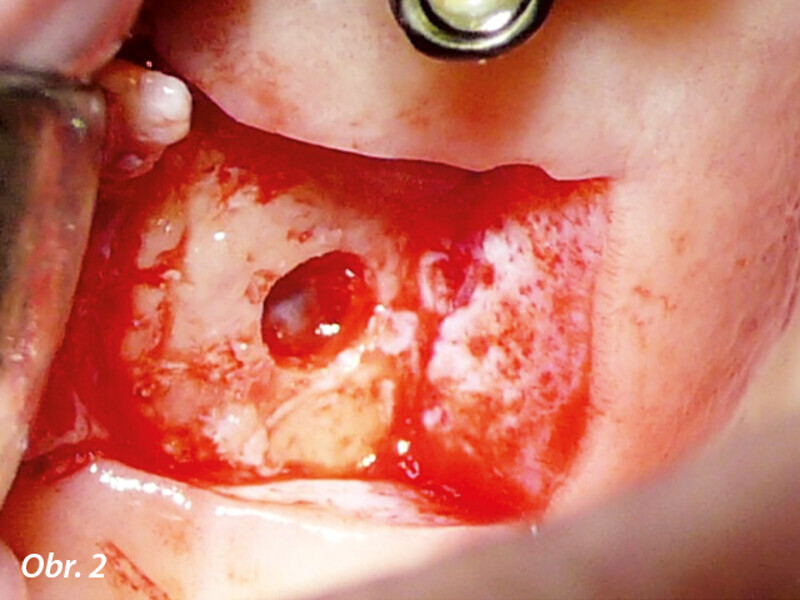

CBCT kostní denzitometrie pro rozhodování před chirurgickým zákrokem